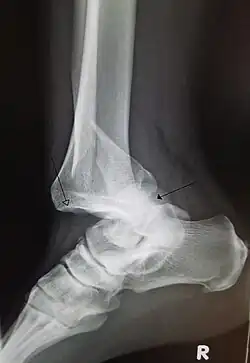

A traumatic dislocation of the tibiotarsal joint of the ankle with distal fibular fracture. Open arrow marks the tibia and the closed arrow marks the talus.